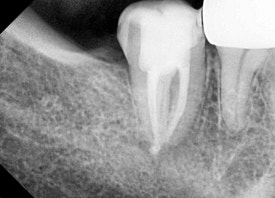

타원에서 받은 신경치료에 염증이 재발해서 재신경치료를 시행한 사례입니다.

일반 신경치료 뿐 아니라

염증이 재발한 신경치료를 다시 하는 것도 좋아합니다.

어려운 케이스는 미세현미경의 도움으로 섬세하게 접근하거나,